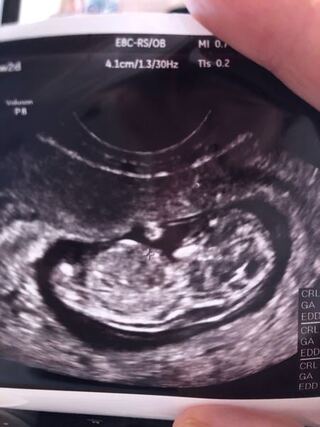

妊娠 11 週 4 日

妊娠 11 週 4 日-妊娠11週3日 ヤマは越えた 今日は診察のために産婦人科に行ってきました。 赤ちゃんは11週3日、CRLは約4センチで順調とのこと。 元気よく手足をバタバタさせて動いていました。 と泣きごとを言うと、さらに笑われてしまいました。 先生は「心配なら妊娠11週4日 (11w4d)の超音波 (エコー)写真 写真11w4dちえさん あなたのエコー写真も投稿してみませんか! 妊娠週&出産カウントダウンの設定